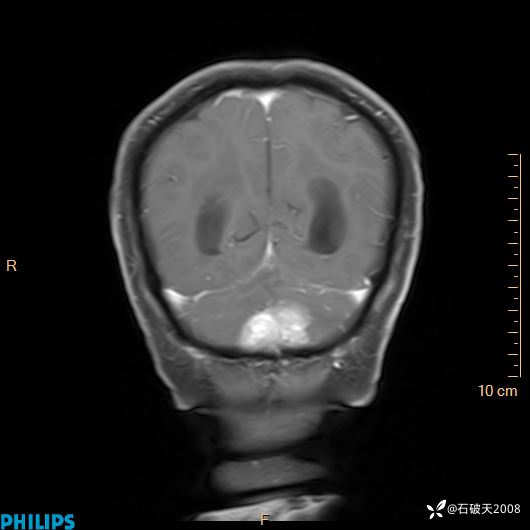

书上说这个肿瘤发生在幕下仅4.09%,你会想到它吗?(病理已公布)

增强冠状位